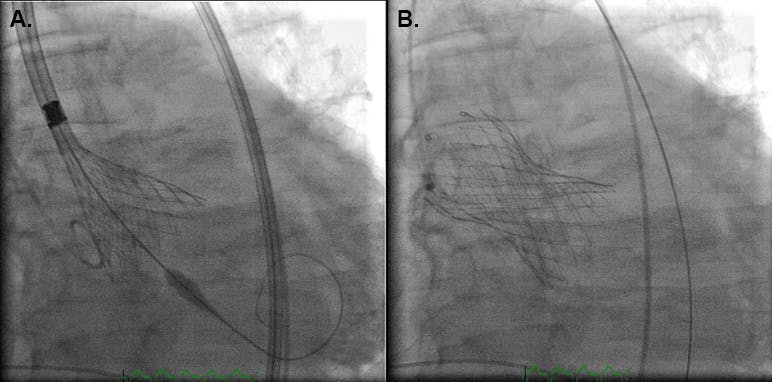

The patient underwent TAVR with a 29-mm Evolut R valve (Medtronic) with 9% oversizing (Figure 3), resulting in no residual stenosis or perivalvular aortic insufficiency (Figure 4). This patient lived for 10 years after TAVR and died from natural causes.

Figure 4. Imaging after the 29-mm Evolut R valve was deployed demonstrated a perfect outcome, with no residual stenosis or perivalvular aortic insufficiency.